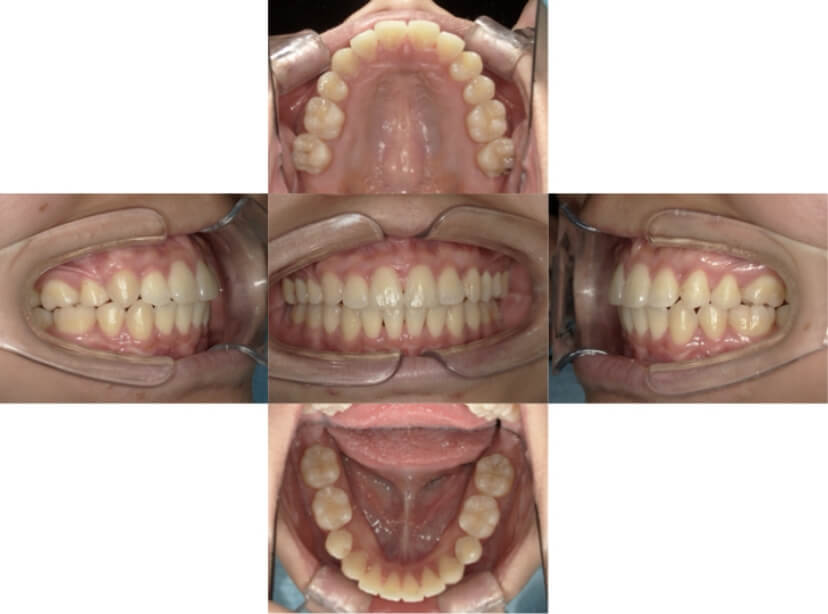

BEFORE

AFTER

上下顎叢生(上下の前歯のガタガタ)のケースです。

装置はラビアル(上下表側)で、上下顎の小臼歯を4本抜歯を行っています。抜歯したスペースを使って、上下の前歯の後方移動と叢生(ガタガタ)の改善を行っています。

主訴 八重歯を治したい。

年齢・性別 25歳 女性

治療方針 抜歯スペースを利用して上前歯の叢生(ガタガタ)の改善

抜歯部位 上下顎左右第一小臼歯

使用装置 ラビアル(上下表側)、顎間ゴム

治療期間 1年11か月

治療回数 16回

リテーナー クリアリテーナー